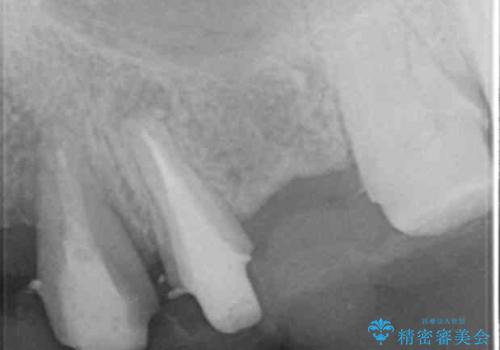

牽引により歯の保存が可能となり、ブリッジによる補綴を行うことができました。

健全歯質を歯肉縁上に出すためにしっかり挺出させたことで歯根長が短くなりましたが、仮歯で十分に保定した結果動揺度Ⅰ程度となり、ブリッジの支台歯にすることが可能と判断しました。

患者様には「抜歯適応の歯を残せて嬉しいし、とても丁寧に治療して頂けた」と大変喜んで頂けました。